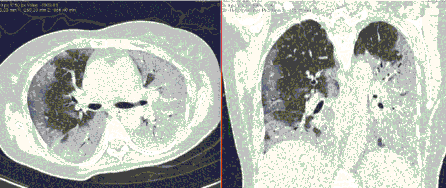

4.3. ЛУЧЕВАЯ ДИАГНОСТИКА COVID-19

Методы лучевой диагностики применяют для выявления COVID-19 пневмоний, их осложнений, дифференциальной диагностики с другими заболеваниями легких, а также для определения степени выраженности и динамики изменений, оценки эффективности проводимой терапии.

Лучевые методы также необходимы для выявления и оценки характера патологических изменений в других анатомических областях и как средства контроля для инвазивных (интервенционных) медицинских вмешательств.

К методам лучевой диагностики патологии ОГК пациентов с предполагаемой/установленной COVID-19 пневмонией относят:

- Обзорную рентгенографию легких (РГ),

- Компьютерную томографию легких (КТ),

- Ультразвуковое исследование легких и плевральных полостей (УЗИ).

Стандартная РГ имеет низкую чувствительность в выявлении начальных изменений в первые дни заболевания и не может применяться для ранней диагностики. Информативность РГ повышается с увеличением длительности течения пневмонии. Рентгенография с использованием передвижных (палатных) аппаратов является основным методом лучевой диагностики патологии ОГК в ОРИТ. Применение передвижного (палатного) аппарата оправдано и для проведения обычных РГ исследований в рентгеновском кабинете. В стационарных условиях относительным преимуществом РГ в сравнении с КТ являются большая пропускная способность. Метод позволяет уверенно выявлять тяжелые формы пневмоний и отек легких различной природы, которые требуют госпитализации, в том числе направления в ОРИТ.

КТ имеет высокую чувствительность в выявлении изменений в легких, характерных для COVID-19. Применение КТ целесообразно для первичной оценки состояния ОГК у пациентов с тяжелыми прогрессирующими формами заболевания, а также для дифференциальной диагностики выявленных изменений и оценки динамики процесса. КТ позволяет выявить характерные изменения в легких у пациентов с COVID-19 еще до появления положительных лабораторных тестов на инфекцию с помощью МАНК. В то же время, КТ выявляет изменения легких у значительного числа пациентов с бессимптомной и легкой формами заболевания, которым не требуется госпитализация. Результаты КТ в этих случаях не влияют на тактику лечения и прогноз заболевания при наличии лабораторного подтверждения COVID-19. Поэтому массовое применение КТ для скрининга асимптомных и легких форм болезни не рекомендуется. При первичном обращении пациента с подозрением на COVID-19 рекомендуется назначать КТ только при наличии клинических и инструментальных признаков дыхательной недостаточности (SpO2 < 95%, ЧДД > 22).

15. Рекомендации по формированию описаний и оценке изменений в легких и ОГК при имеющейся/подозреваемой пневмонии COVID-19 представлены в Приложении 1.